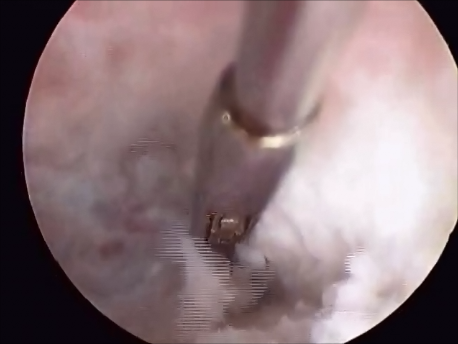

- Intrauterine foreign bodies: Missing copper T embedded in the uterine wall or retained fetal bones or pregnancy following a miscarriage can contribute to irregular bleeding, infection or subfertility.